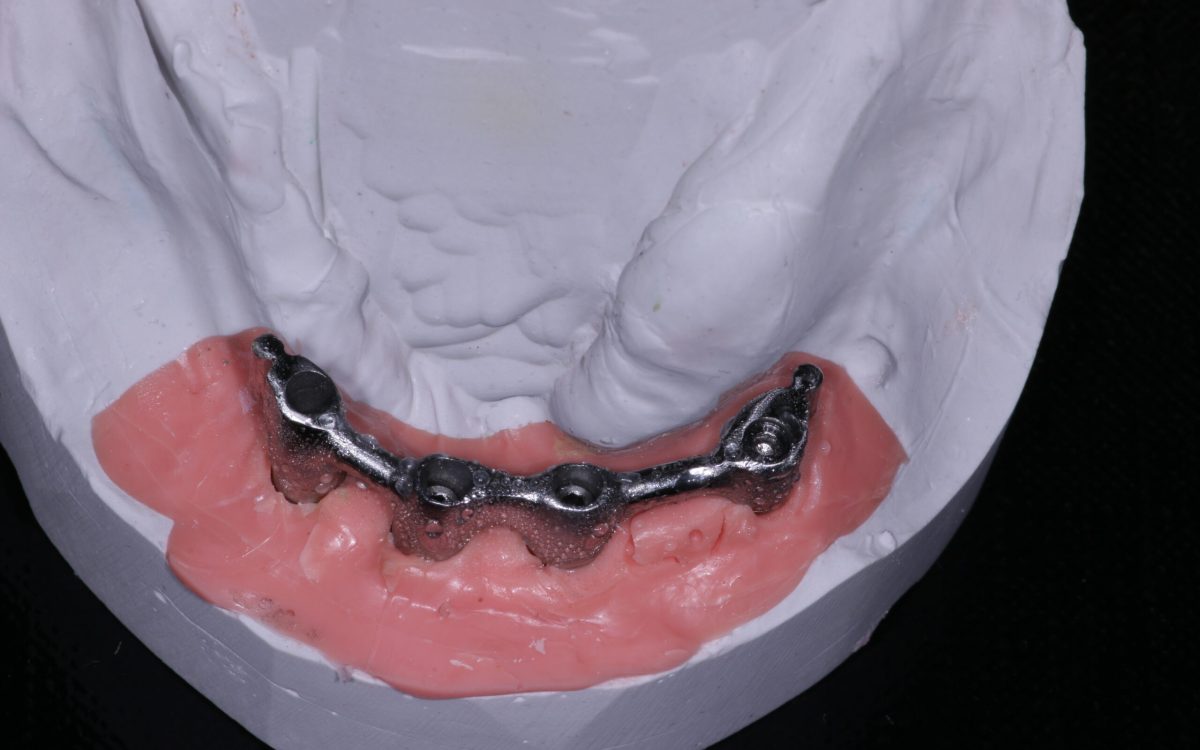

- Overdenture fogpótlás – implantátumokon rögzített fogsor

Az implantátum egy titániumból készült foggyökér formájú csavar, amit a foghiány helyére ültetünk be az állcsontban. Becsontosodása után kerül rá egy implantátum felépitmény és arra a fogpótlás, vagyis a korona. Jelenleg az egyik legmodernebb fogpótlási megoldás.

Implantátummal egy, vagy több fogat is lehet pótolni. Előnye, hogyha csak egy foghiány pótlására van szükség, akkor a mellette lévő fogakat nem kell lecsiszolni, mint a hagyományos pótlások esetében. Több foghiány esetén 2-4-6 implantátummal már 3 fog hiányától egész fogatlanságig pótloható a fogazat. Léteznek olyan implantátumok is, melyek a fogsorok stabilitását javítják.

- Beültetjük az implantátumo(ka)t, ami után minimum 4 hónapos gyógyulási időszak következik.

- A gyógyulási idő letelte után az íny alatt lévő implantátumokat feltárjuk. Gyógyulási csavart helyezünk be, mely segít az implantátum körüli íny formázásában.

- Egy lenyomati fej segítségével lenyomatot veszünk.

- 2-3 próba után az implantátum fejre kerül a végleges, fogtechnikai labor által készített pótlás (korona, híd), ami általában további 1,5-2 hetet vesz igénybe.